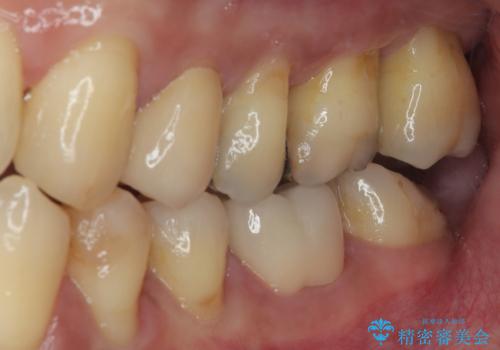

審美面、機能面共に満足していただけました。

順次、後ろにある不適合のメタルインレーの部位をやり替えていく予定です。